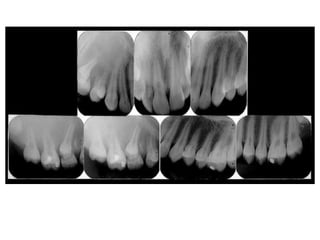

Cementa-osseous dysplasia. low-power photomicrograph showing fragments of

cellular fibrous connective tissue conta in ing scattered trabeculae of bone.

Cementa-osseous dysplasia. High-power photomicrograph showing spicules

of bone and cementum-like hard tissue within moderately ce llular fibrous

connectivet issue, Note the hemorrhage around t he bony trabeculae.